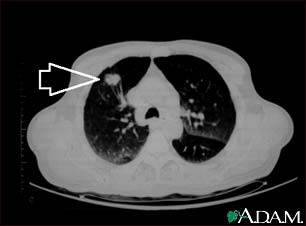

Lung mass, right upper lobe - CT scan

This is a CT scan of the upper lungs. This individual has a mass in upper part of the right lung (left side of picture).